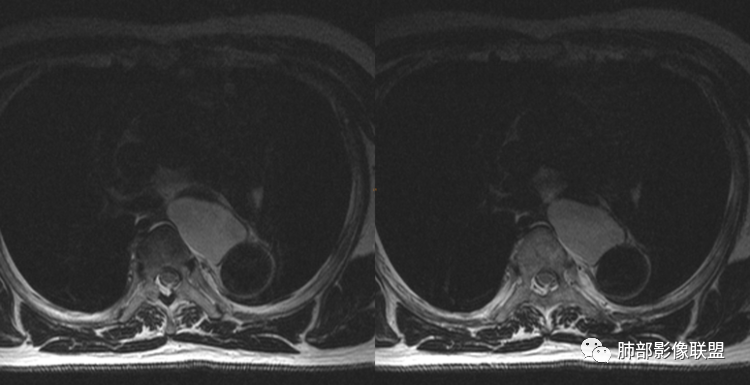

男性,43岁,体检发现后纵隔占位,边缘光整,CT示密度均匀,周围组织受压移位,无钙化囊变及脂肪组织,增强未见明显强化。MRI:T1示肿块信号较肌肉高,T2不均匀高信号。考虑为良性病变,第一是神经节细胞瘤,其次是支气管源性囊肿。

中年男性,无症状,后纵隔肿块,长径大矢状位于横径,质地偏软,塑形,等t1稍长t2,比较均质,增强轻微强化,与脊柱,主动脉,食管脂肪间隙存在,部分层面与脊柱相贴,骨质无改变,周围无肿大淋巴结,考虑神经源性肿瘤,节细胞神经瘤可能大,鉴别心包斜窦,淋巴瘤,淋巴管囊肿。

后纵隔占位,椭圆形,边缘不规则,CT低密度,MRI长稍长T1稍长T2信号,增强扫描未见强化,支气管受压。囊性病变,考虑支气管囊肿(常见,T1WI稍低“比水高”T2WI稍高,可能与其内含有粘液或蛋白有关);鉴别淋巴管囊肿(更软塑性性更大,接近纯水MRI信号长T1长T2,受周围挤压更明显,变形。);神经节细胞瘤瘤(增强可有轻度渐进性强化,也可不强化,关键是不常见),还有就是神经源性囊肿与肠源性性囊肿。

后纵隔占位;食道向右侧推移,病变质软,CT平扫密度均匀,边缘清晰光整,MRI 稍长T1,长T2高,脂肪抑制高信号。考虑纵隔良性囊性占位。先考虑支气管囊肿。其它类囊肿待除外。